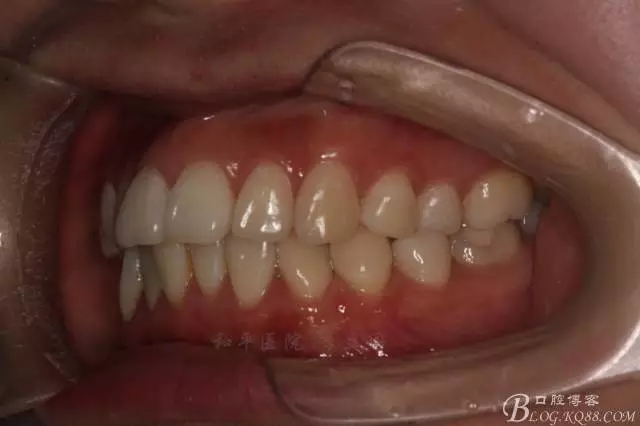

該病例主要為17、27頰側(cè)位同時伴有伸長,當然種植支抗可以解決,但還有簡單實用的辦法嗎?如圖,在橫腭桿遠中延伸出牽引鉤,位置盡量遠離合平面,7粘舌側(cè)扣,牽引力的方向為壓低及舌向,下圖為兩個月的效果,17已到位,27還未到位。